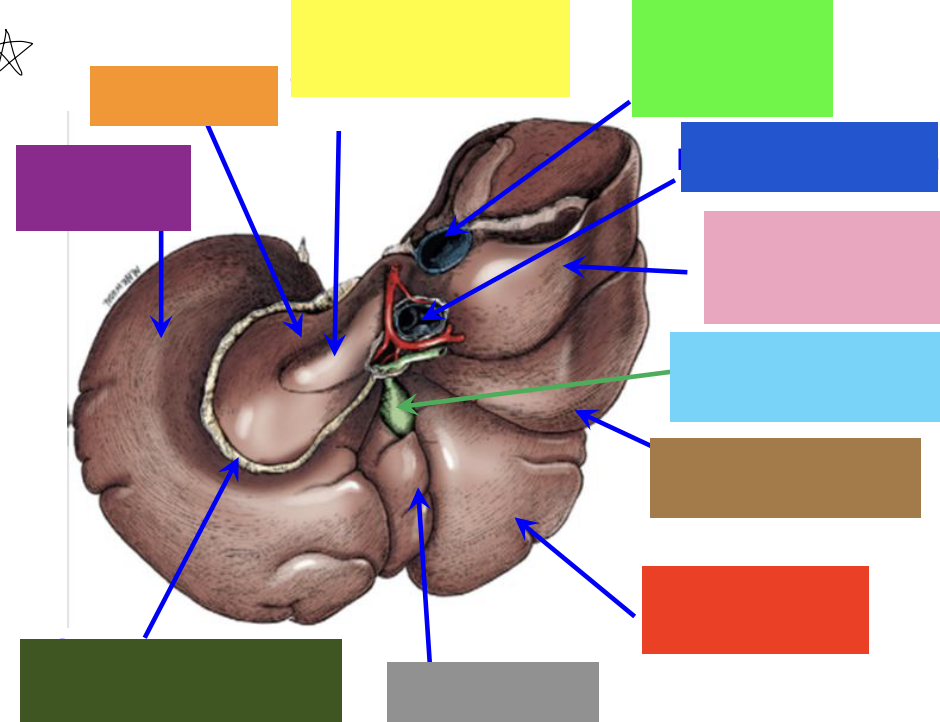

purple box

left lateral lobe

orange box

caudate lobe

yellow box

papillary process of the caudate lobe

neon green box

right lateral lobe

dark blue box

hepatic portal vein

pink box

caudate process of the caudate lobe

light blue box

gall bladder

brown box

right lateral lobe

red box

right medial lobe

grey box

quadrate lobe

dark green box

lesser omentum